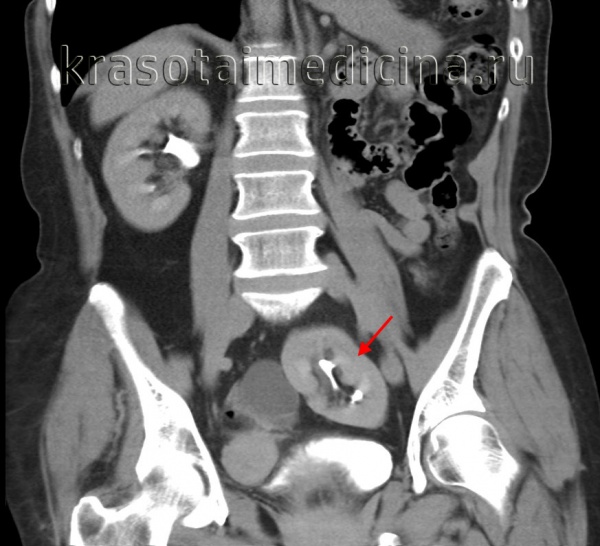

КТ, корональная реформация. Агенезия правой почки.

Слияние почек на одной стороне встречается с частотой 1 на 1000 новорожденных явным преобладанием мужчин. Некоторые авторы по форме и локализации выделяют 6 подтипов. Аномалия видна любым из лучевых методов, но при КТ лучше оценивается положение мочеточников и взаимотношение с соседними структурами.

Тазовое расположение почки встречается с частотой 1 на 3000, что делает этот вариант одним из наиболее распространенных почечных эктопий. Обычно протекает бессимптомно. Хорошо определяется любым лучевым методом